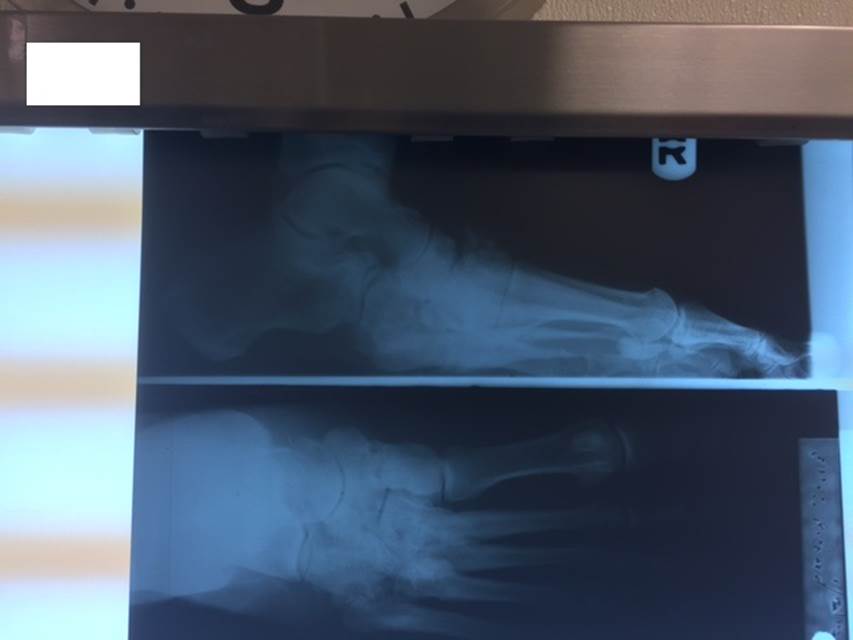

"Surgical misadventure" by another surgeon about 8 years ago. The wrong fixation was used for a flatfoot repair, & the deformity was not corrected. Patient came in with severe foot & ankle pain, with no arch at all. She was unable to play with her grandchild because the pain was so bad, & because she felt unsteady. The old hardware was removed, a lateral calcaneal lengthening osteotomy was performed along with a medial column/1st ray realignment. The ankle was painfully arthritic, & patient elected a total ankle replacement vs. an ankle fusion. She is now able to walk pain free & play with her grandchildren!